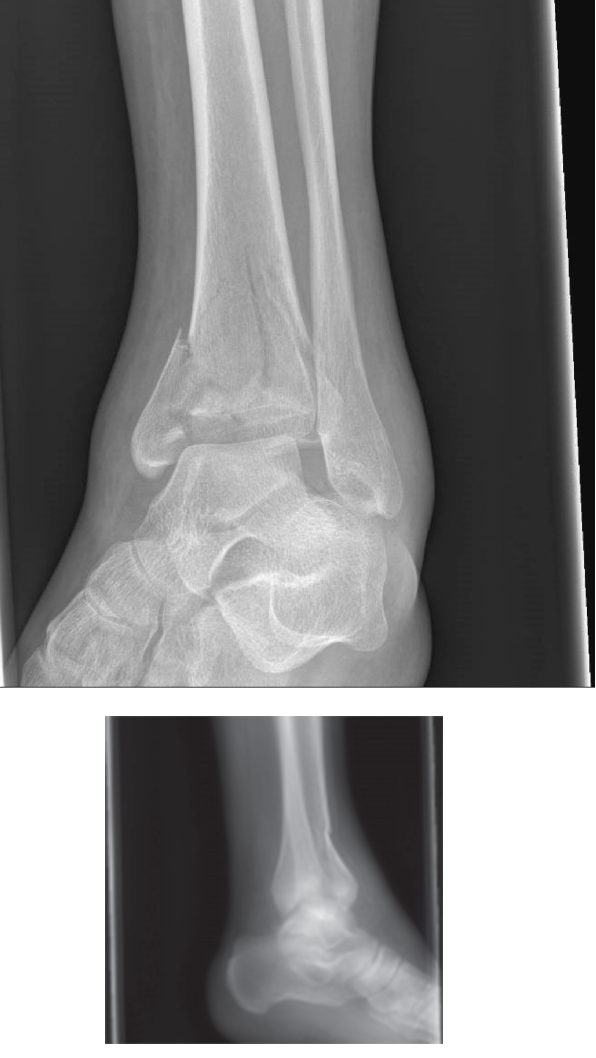

A 29-year-old woman arrives to the emergency department after jumping from the second story of a burning buil…

Describe the radiographs pictured above. These are AP and lateral radiographs showing a comminuted and displa…